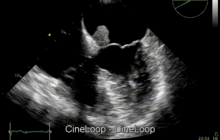

Echocardiogram of Atrial myxoma